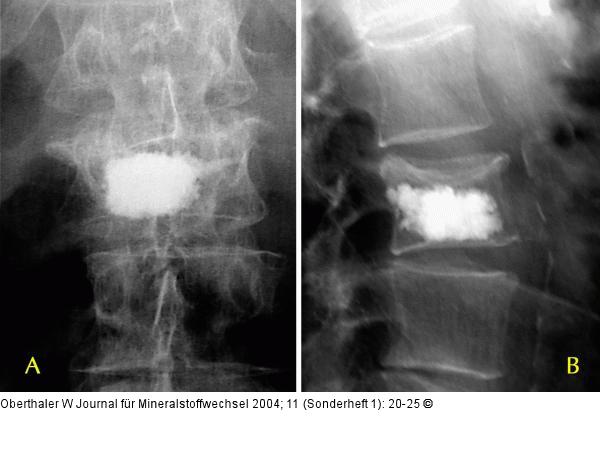

Abbildung 9a-b: Vertebroplastie Korrekte Füllung des Wirbelkörpers durch Vertebroplastie mit 1 Kanüle |

Abbildung 9a-b: Vertebroplastie

Korrekte Füllung des Wirbelkörpers durch Vertebroplastie mit 1 Kanüle |